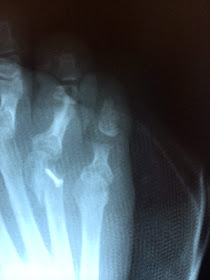

Okay . . . here is one of my post-op x-rays.  They didn't remove my cast so this shot was taken through the cast and all the bandaging on these two toes.  These are the two toes he worked on.

The 4th toe has the screw in the metatarsal head where it connects to the "toe-bones" (or phalanges)  that he put in to help hold it in place (it has dislocated again).  Also, the white in the bone above that screw extending to the next bone is some sort of an implant to keep those bones aligned.  Got to admit this 4th toe still looks pretty crooked here, and I'll be talking with the doctor about it.  It may simply be the bandaging that is causing it to appear this way.

To the right is the little toe.  If you count toe bones you'll find one is missing!  He removed the middle phalanges . . . that is the dark space where it use to be!)  What you can't see is that he re-set the metatarsal / proximal phalanges joint on the little toe and he also cut the tendon on the bottom that was making my toe stick down rather than stick out straight!!  LOL!